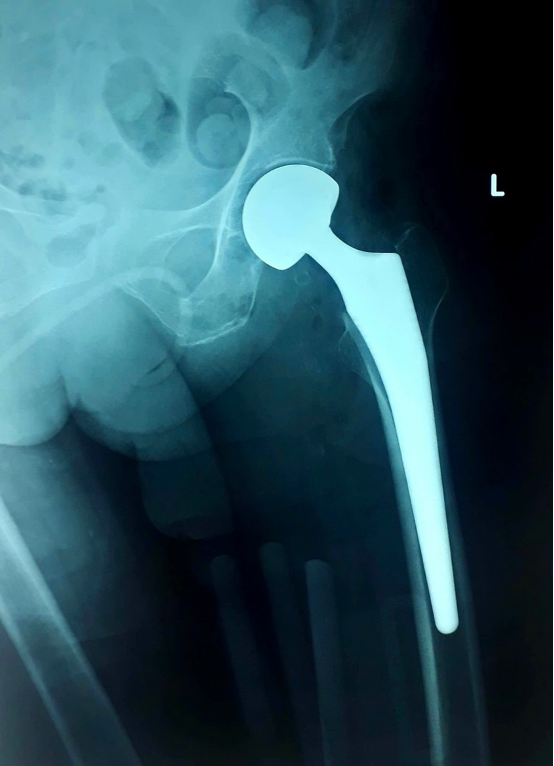

BS.CKII Hà Nguyên Minh Quang – Trưởng khoa Ngoại Chấn thương – Chỉnh hình, Bệnh viện Hoàn Mỹ Đà Nẵng cho biết: bác H bị gãy cổ xương đùi trái, còn bác G và T cùng gãy liên mấu chuyển xương đùi. Nguyên nhân dẫn đến chấn thương đều do té ngã trong sinh hoạt, và đây cũng là một trong những nguyên nhân chấn thương thường gặp nhất ở người cao tuổi. Người bệnh nhập viện trong tình trạng sưng đau bên háng, bầm tím, gần như không thể cử động.

Đối với trường hợp gãy đầu trên xương đùi (chỏm xương đùi, cổ xương đùi, vùng mấu chuyển và vùng dưới mấu chuyển) ở người cao tuổi, có 2 phương pháp điều trị phổ biến là cố định ổ gãy bằng phương tiện và thay khớp háng. Trong đó, thay khớp háng là phương pháp tối ưu, tránh biến chứng loét do tì đè nằm lâu, nhiễm trùng tiết niệu và phục hồi vận động sớm.

Mặc dù thay khớp háng là lựa chọn tối ưu cho người bệnh trong 3 trường hợp này, tuy nhiên do bệnh cao tuổi, nhiều bệnh nền mãn tính như: tăng huyết áp, viêm phổi, bệnh tim thiếu máu cục bộ mạn tính, đái tháo đường type 2, rối loạn mỡ máu, suy thận mạn, thoái hóa khớp,... Do vậy, để phẫu thuật thay khớp háng diễn ra an toàn, trước mỗi ca phẫu thuật ekip tiến hành đánh giá toàn trạng người bệnh, hội chẩn đa khoa, phân tầng nguy cơ tim mạch, đột quỵ, thuyên tắc huyết khối. Phẫu thuật cũng đòi hỏi sự phối hợp chặt chẽ của ekip gây mê hồi sức, bác sĩ ngoại khoa, kỹ thuật viên phục hồi chức năng từ giai đoạn tiền phẫu đến quy trình chăm sóc, phục hồi chức năng sau mổ nhằm đảm bảo an toàn trong và sau phẫu thuật cho người bệnh. Sau khi hội chẩn, đánh giá, chuẩn bị cho mọi nguy cơ, các bác sĩ quyết định lựa chọn phẫu thuật thay khớp háng điều trị gãy đầu trên xương đùi cho cả 3 người bệnh.

Phẫu thuật thay khớp háng bằng đường mổ ít xâm lấn tại Bệnh viện Hoàn Mỹ Đà Nẵng là một phẫu thuật thường quy được ứng dụng hiệu quả trong điều trị gãy xương ở người cao tuổi cho thời gian phẫu thuật ngắn, ít tổn hại mô mềm xung quanh, giúp người bệnh phục hồi sớm, có thể đi lại nhẹ nhàng sau 1 tuần, giảm thiểu các biến chứng sau phẫu thuật.